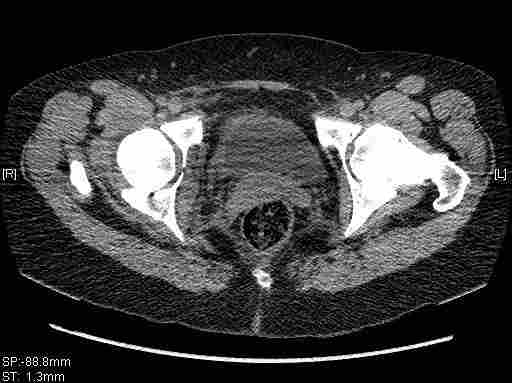

Удалось сегодня вывести пациентку в соседнюю больницу, где есть кт. Срезы сделаны только горизонтальные.